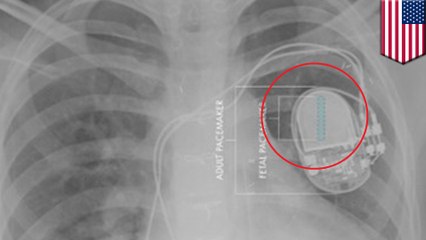

World’s Smallest Pacemaker, the Size of a Rice Grain, Marks Major Medical Breakthrough